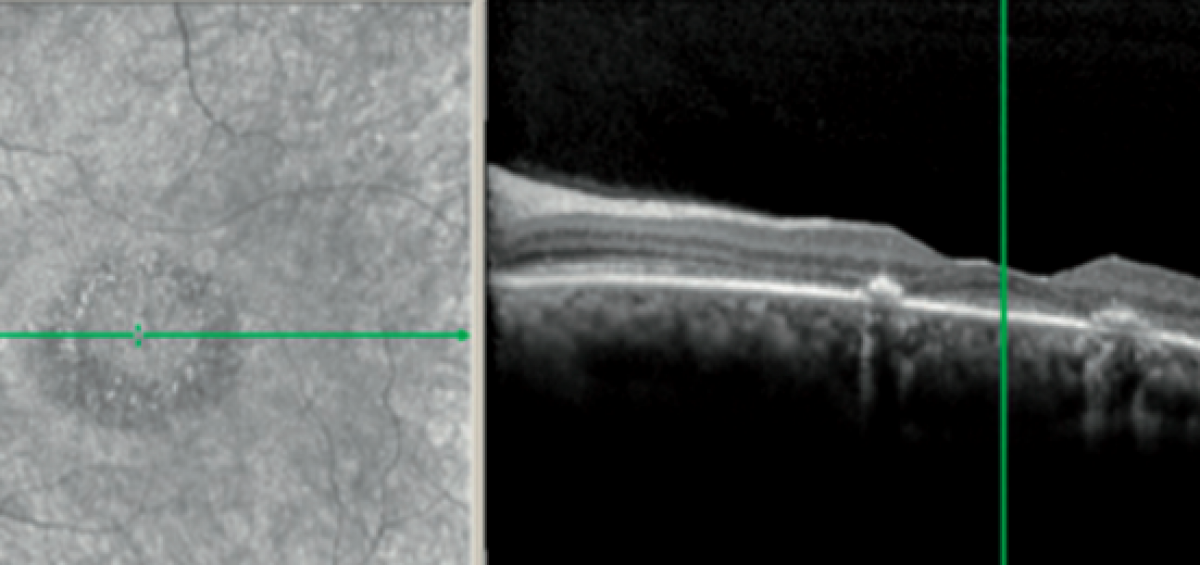

L’idrossiclorochina, utilizzata per il trattamento di malattie autoimmuni, come l’artrite reumatoide e lupus eritematoso, e può causare patologie retiniche non reversibili. Alcuni studi scientifici hanno dimostrato che l’utilizzo a lungo termine, almeno 5 anni, di idrossiclorochina ha pochi effetti collaterali sistemici ma può portare a danni irreversibili alla retina. Tuttavia, la retinopatia e la maculopatiaRead more